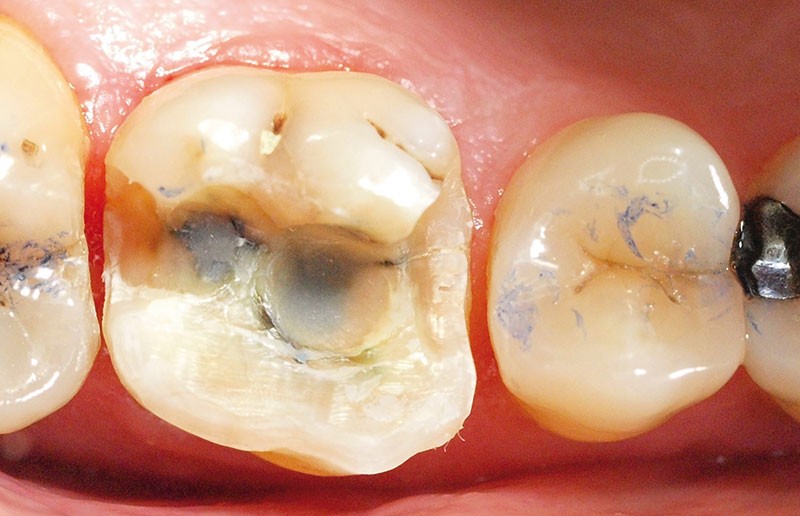

Voilà 6 mois, une patiente se présente à notre cabinet au motif d’une douleur récurrente sur le secteur molaire supérieur droit lors de la mastication. Une anamnèse rapide et cadrée est réalisée pour optimiser le temps passé et avancer les éléments diagnostiques. La patiente décrit une gêne ancienne, déclenchée essentiellement par la mastication. À l’auscultation, les examens endo-buccaux et radiologiques montrent une denture superbe avec très peu de soins, une hygiène buccale sans reproche, et des fonctions manducatrices saines [1] (fig. 1 et 2).

Ce jour-là, aucun diagnostic précis n’est posé concernant cette perception douloureuse. Aussi, nous proposons à la patiente de réévaluer cette sensibilité en fonction de son évolution, et au plus tard sous six mois. Lors de cette consultation de réévaluation, la patiente se présente avec la même doléance, majorée de quelques signes : la douleur, toujours furtive, est plus régulièrement présente, augmentée en puissance (nous n’avons malheureusement pas noté d’échelle d’évaluation douloureuse comparative), mais également déclenchée par la pression dento-dentaire (sans présence d’aliment). En complément, la patiente confirme que cette douleur est plus importante lors de la dépression, du relâché de l’occlusion que lors de la pression [2]. Comme six mois auparavant, la patiente présente un bon état de santé général, n’a ni rhume ni sinusite. L’anamnèse est donc complétée et, grâce à un protocole rigoureux [3], elle nous permet de découvrir aussi des céphalées, des douleurs musculaires et cervicales récurrentes malgré l’intervention d’un ostéopathe. En poussant plus loin l’échange, la patiente déclare une très importante période de stress depuis neuf mois, et nous mettons en évidence une attitude de contacts…